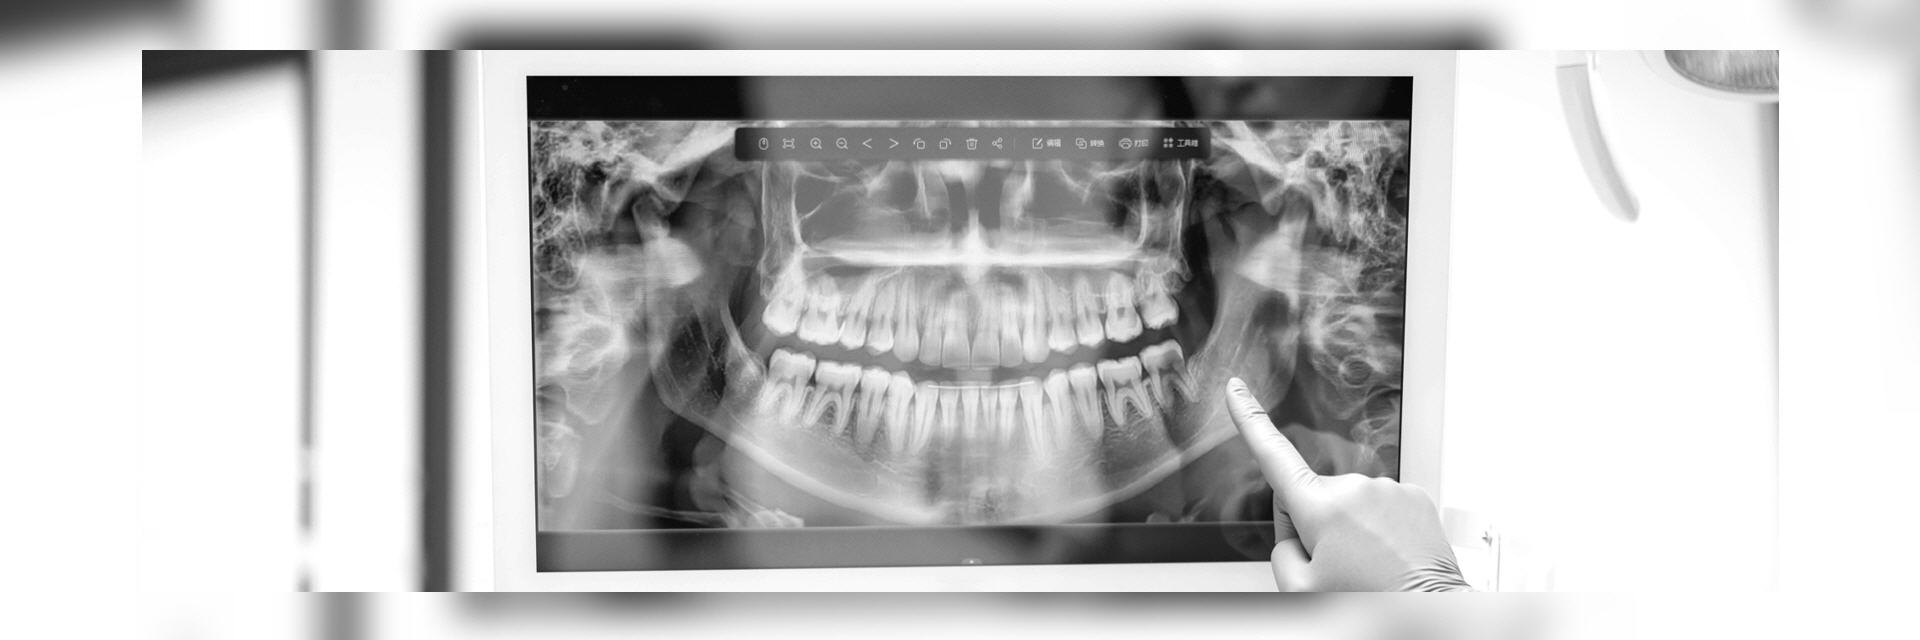

Im digitalen Röntgenbild sehen wir die Vorgeschichte Ihrer Zähne. Also die Spuren des Lebens, die dieses an den Zähnen hinterlassen hat. Dies betrifft Erkrankungen wie die Karies, Spalten unter Kronen oder Füllungen, Wurzelbehandlungen, Entzündungen im Knochen, aber auch Beläge und deren Auswirkungen auf den Zahnhalteapparat also den umgebenden Knochen.

- Orthopantomogramm (OPG) ist eine Panoramaschichtaufnahme des gesamten Ober- und Unterkiefers inkl. der Kiefergelenke in 2-dimensionaler Darstellung. Das Verfahren ist schmerzfrei, strahlenarm und auch bei Würgereiz problemlos durchführbar. Dieses Bild gibt dem Zahnarzt eine Gesamtübersicht und ermöglicht eine Beurteilung der Zahnzwischenräume, der im Knochen befindlichen Wurzeln,